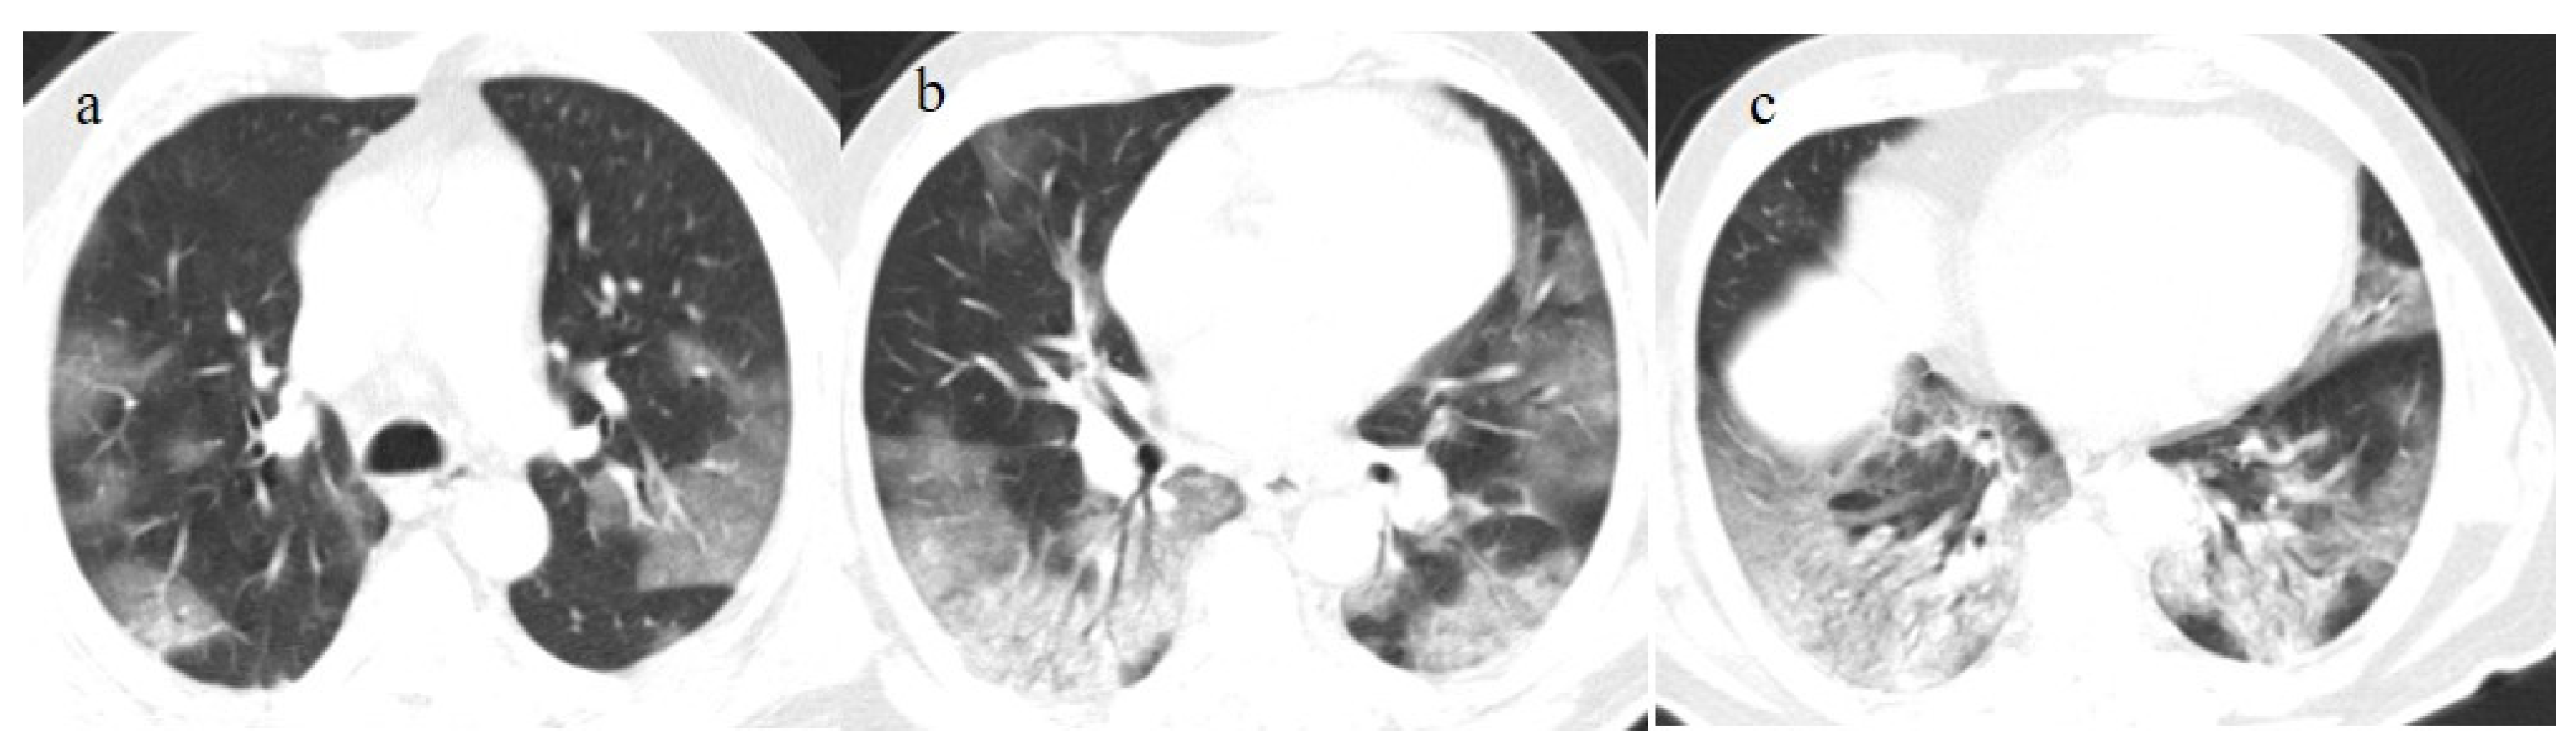

3.3.3. Pulmonary Fibrosis

- Kanne, J.P.; Little, B.P.; Schulte, J.J.; Haramati, A.; Haramati, L.B. Long-term Lung Abnormalities Associated with COVID-19 Pneumonia. Radiology 2023, 306, e221806. [Google Scholar] [CrossRef]

- Han, X.; Fan, Y.; Alwalid, O.; Zhang, X.; Jia, X.; Zheng, Y.; Shi, H. Fibrotic Interstitial Lung Abnormalities at 1-year Follow-up CT after Severe COVID-19. Radiology 2021, 301, E438–E440. [Google Scholar] [CrossRef]

- Watanabe, A.; So, M.; Iwagami, M.; Fukunaga, K.; Takagi, H.; Kabata, H.; Kuno, T. One-year follow-up CT findings in COVID-19 patients: A systematic review and meta-analysis. Respirology 2022, 27, 605–616. [Google Scholar] [CrossRef]

| Typical Appearance | GGOs with a crazy-paving pattern and consolidations in a peripheral and posterior or central-peripheral distribution; multilobar involvement; vascular enlargement, the halo and reversed halo sign; subpleural and parenchymal bands; and architectural distortion. They were predominant since the Delta wave. |